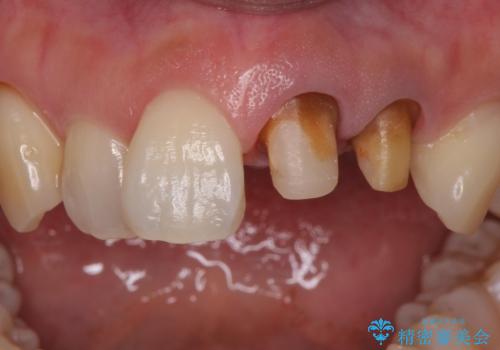

- 前歯の変色を主訴に来院された患者様です。

再根管治療からのやり直しも提案しましたが、特にご希望されなかったためクラウンでの修復処置のみ行います。

- 左上12 : 仮歯 / 11,000円×2、ジルコニアクラウン(スタンダード) / 121,000円×2 合計264,000円費用は治療当時の料金となります

歯は根管治療が終了して時間が経つとだんだん茶色く変色していきます。